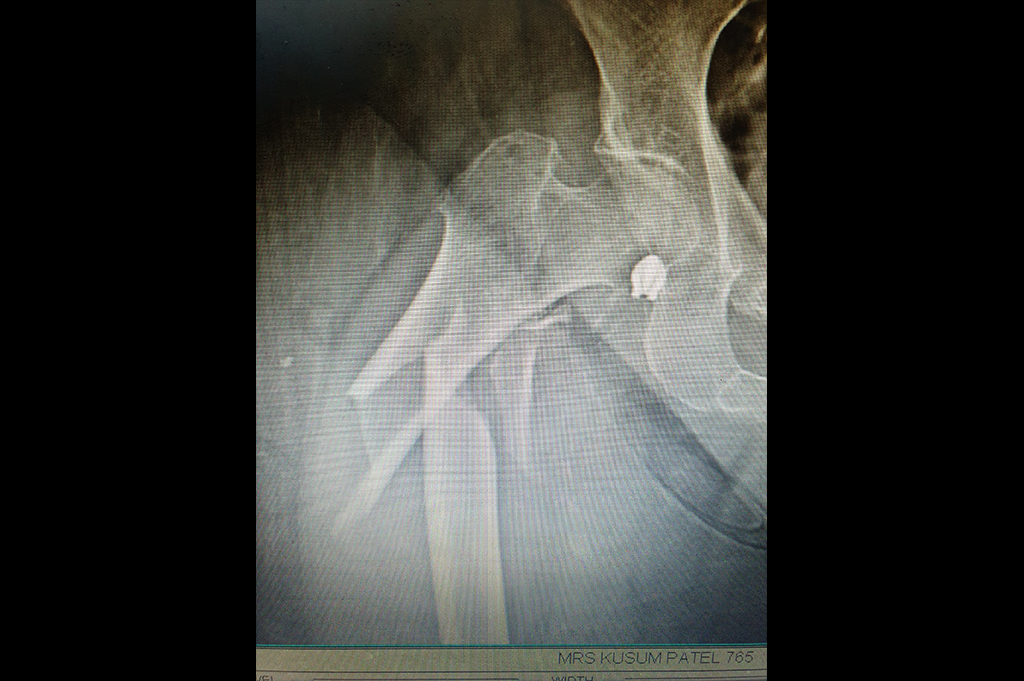

Intertrochanteric Fracture